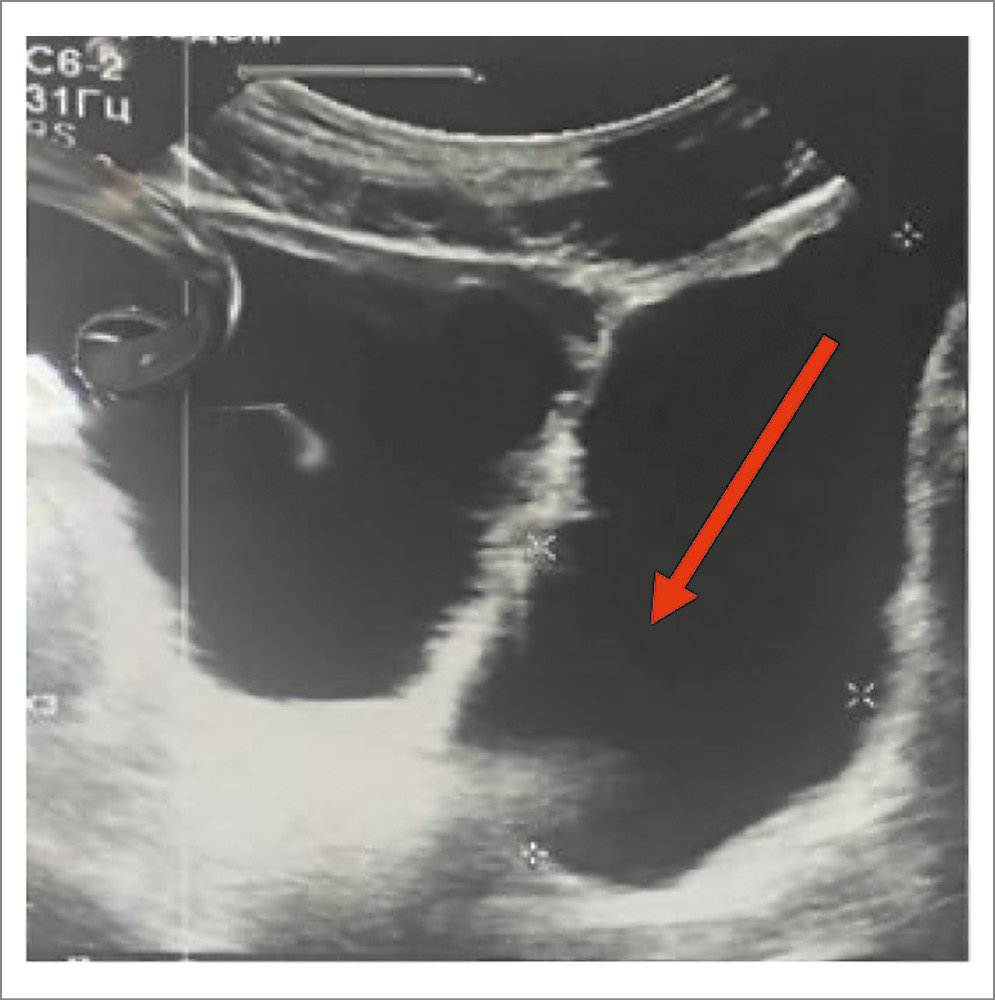

Пациент В., 68 лет, обратился за медицинской помощью с жалобами на боль в левой подвздошной области, чувство неполного опорожнения мочевого пузыря, слабую струю мочи на протяжении 8 мес. При УЗИ на левой стенке мочевого пузыря выявлен дивертикул, объем которого колебался в пределах от 400 до 700 мл. Объем мочевого пузыря составил 250–350 мл. Количество остаточной мочи в мочевом пузыре составило 56 мл, в дивертикуле – 604 мл (рис. 2).

Рис. 2. Пациент В., ультрасонограмма мочевого пузыря. Стрелкой указан ДМП.